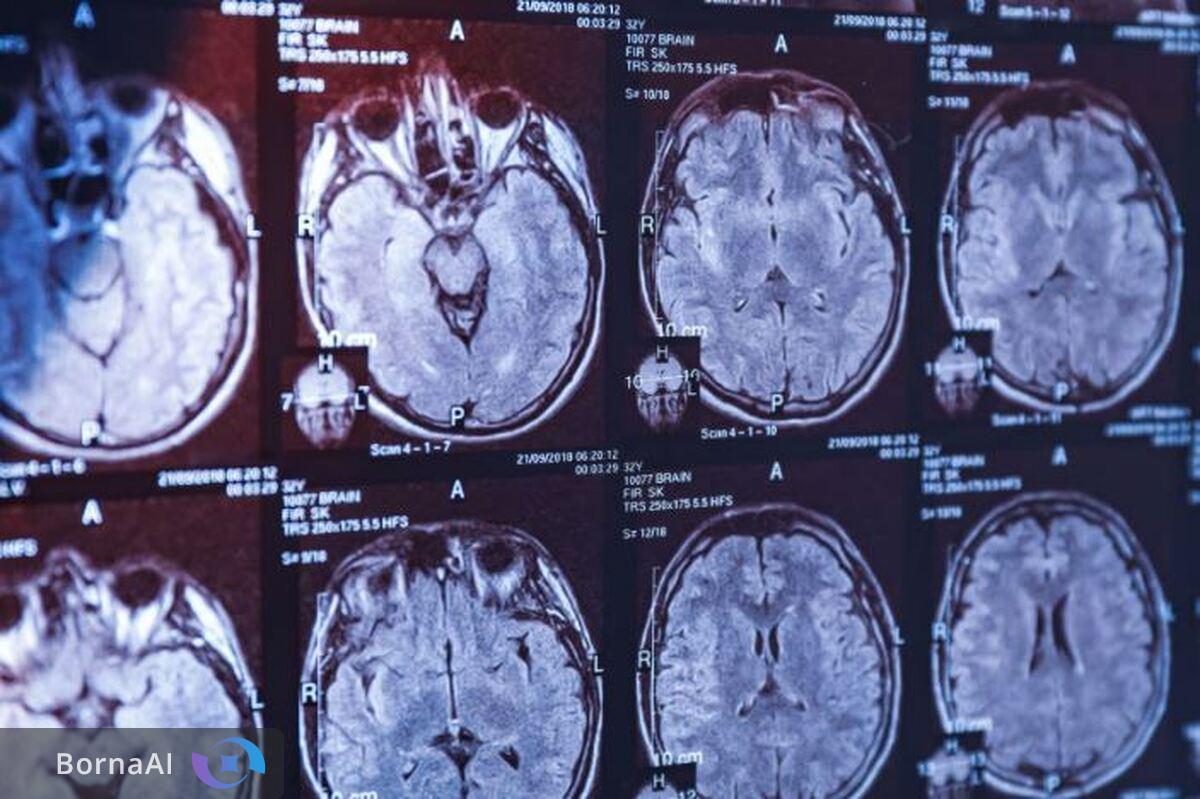

در حوزه سلامت، علوم شناختی به پزشکان و متخصصان این امکان را میدهد که با اتکا به دادههای دقیقتر مغزی و رفتاری رویکردهای درمانی شخصیسازیشدهتری ارائه دهند. تصویربرداریهای پیشرفته مغزی، آزمونهای شناختی استاندارد و تحلیل الگوهای رفتاری همگی ابزارهایی هستند که در پرتو این دانش توسعه یافتهاند. از سوی دیگر افزایش بار بیماریهای عصبی و روانی در جوامع امروزی ضرورت توجه راهبردی به این حوزه را دوچندان کرده است؛ ضرورتی که بدون بهرهگیری از فناوریهای نوین پاسخگویی به آن دشوار خواهد بود.

در حوزه تصویربرداری مغزی یا نوروایمجینگ هوش مصنوعی میتواند کیفیت تصاویر، دقت تشخیص و سرعت تحلیل دادهها را بهطور چشمگیری افزایش دهد. بهبود تفکیکپذیری تصاویر، شناسایی الگوهای پنهان در دادههای مغزی و پیشبینی روند پیشرفت بیماریها تنها بخشی از این کاربردهاست. علاوه بر این هوش مصنوعی در توسعه ابزارهای توانبخشی شناختی، نورواگمنتیشن (Neuro-Augmentation) و بهبود عملکردهای شناختی نیز نقش مهمی ایفا میکند.

از سوی دیگر تمرکز بر کاربردهای عملی هوش مصنوعی در حوزههایی مانند تصویربرداری مغزی، بهبود شناختی و نورواگمنتیشن نشان میدهد که نگاه سیاستگذار صرفا معطوف به تولید مقاله یا دستاوردهای نظری نیست بلکه حل مسائل واقعی نظام سلامت و ارتقای کیفیت زندگی مردم در اولویت قرار دارد.

تمرکز بر کاربست هوش مصنوعی در علوم شناختی بهویژه در حوزههایی مانند ارتقای تصویربرداریهای عصبی، تحلیل پیشرفته دادههای مغزی، بهبود شناختی و توسعه فناوریهای نورواگمنتیشن بیانگر تلاشی آگاهانه برای پیوند دادن دستاوردهای علمی با نیازهای واقعی نظام سلامت و زندگی روزمره مردم است؛ تلاشی که در صورت تداوم و تعمیق میتواند به افزایش کیفیت تشخیص، درمان و توانبخشی در اختلالات شناختی و عصبی منجر شود.